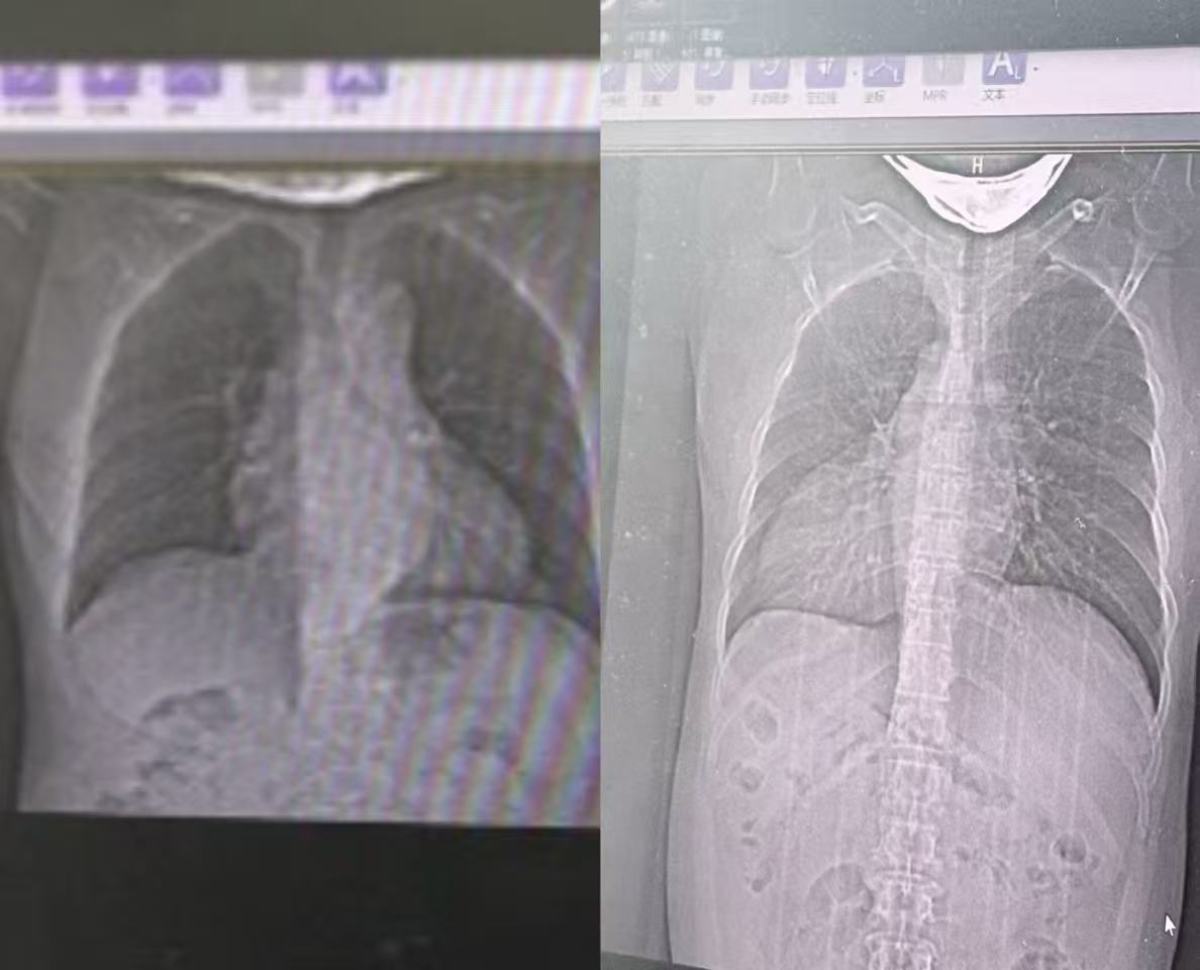

左、右位心脏胸片对比图(胸片为镜像显示,右侧为周先生胸片)